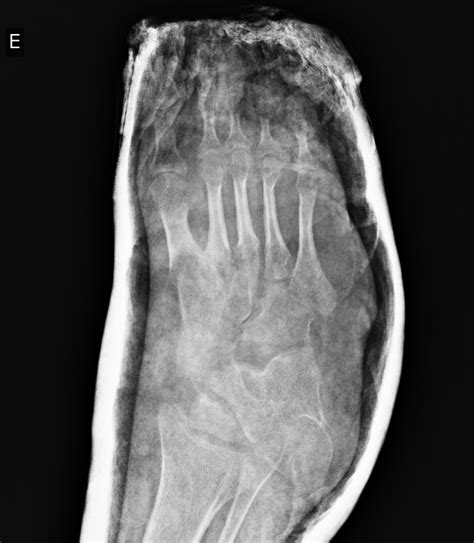

While often associated with infancy and early childhood development, Talipes Equinovarus in adults represents a complex clinical scenario that can significantly impact a person’s mobility, comfort, and overall quality of life. Commonly known as clubfoot, this condition involves a structural deformity where the foot is twisted inward and downward. When this condition persists into adulthood—either as a result of untreated congenital cases, relapse after initial treatment, or secondary causes like neurological disorders—it requires specialized orthopedic intervention to restore function and alleviate chronic pain.

The term Talipes Equinovarus is derived from Latin, where "talus" refers to the ankle, "pes" to the foot, "equinus" to the horse-like position (plantar flexion), and "varus" to the inward inversion. In an adult patient, the foot may appear rigid, making it difficult to place the sole flat on the ground. This rigid deformity is not merely cosmetic; it changes the biomechanics of the entire lower limb, often leading to secondary complications in the knee, hip, and lower back due to compensatory gait changes.

Patients living with Talipes Equinovarus in adults often present with a distinct set of physical challenges. Because the foot is held in an abnormal position, the distribution of weight while walking is severely compromised. This leads to the development of painful calluses on the outer edge of the foot, which is the primary weight-bearing surface.